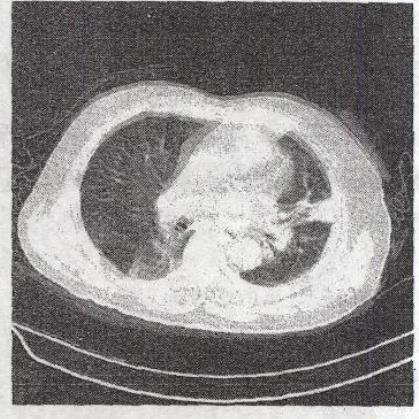

患者发热、咳痰2个月。CT检查如图所示,最可能的诊断是()。

A、支气管扩张

B、肺段隔离症

C、多发转移癌

D、肺炎

E、左肺下叶不张

D